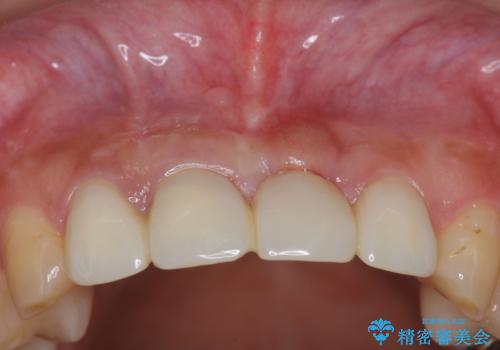

不良インプラントの除去・骨造成・歯肉移植・前歯審美セラミックブリッジ製作

- 前歯の見栄えの悪さの改善を求めて来院されました。

不良インプラントを除去し最終的にブリッジによる補綴で審美性の改善を行うこと、その準備として骨の造成・歯肉の移植による歯の欠損部顎堤のボリュームを維持・増大を計画します。

- 65万円(仮歯・ファイバーコア・ジルコニアクラウン・インプラント除去・骨造成・歯肉移植)費用は治療当時の料金となります